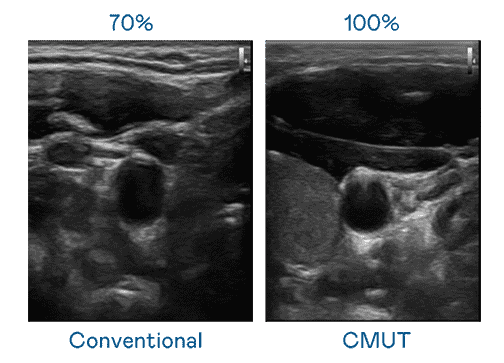

CMUT 技术是一种用电容式微机电元件来产生超音波讯号的技术。。与传统 PZT 压电式技术相比,,,CMUT 频宽增加 30%,,更宽频的超音波讯号让影像解析度大幅提升,,,是实现高影像品质医疗超音波扫描、、、、促进精准医疗发展的关键技术。。。

超音波影像的解析度高低,,,首先取决于探头能发出的讯号频宽。。。。888.BY集团电子游戏 CMUT 可提供高清晰的超音波讯号,,,,提供高频宽、、、高灵敏度、、、影像纹理细节更高的超音波影像,,,,协助医护人员缩短影像判读时间及利用精准的医疗影像进行诊断。。。。